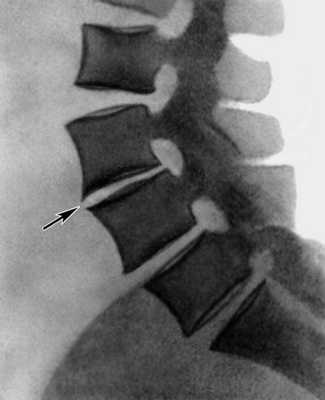

- хрящевые узлы тел позвонков (грыжи Шморля) определяются в телах L и являются одним из проявлений дистрофических поражений в двигательных сегментах позвоночника и свидетельствуют о пролабировании фрагментов межпозвоночного диска в тело позвонка;

- дегенеративно - атрофические изменения, отражающие распад межпозвонкового диска с разрушением замыкающих пластинок тел позвонков и внедрением элементов распавшегося диска в тела позвонков в виде мелких узелков Поммера, что свидетельствует о функциональной неполноценности межпозвонковых дисков сегментов L – L ;

- хрящевые узлы тел позвонков (грыжи Шморля) в телах L и являются признаком анатомической и функциональной несостоятельности межпозвонковых дисков в сегментах L ;